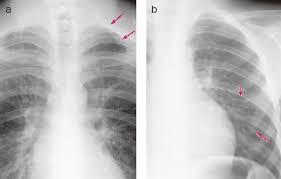

진단 방법

갈비뼈의 미세 손상은 단순 엑스레이(X-ray)로 잘 보이지 않는 경우가 많습니다. 이 경우 CT(컴퓨터 단층촬영) 또는 초음파 검사가 보조적으로 사용될 수 있습니다. 의사는 병력 청취와 촉진검사를 통해 통증 부위를 확인한 뒤, 필요한 경우 정밀 진단을 권합니다.